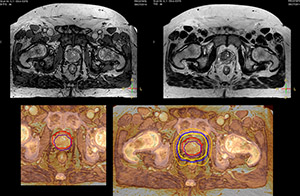

The potential benefits of using MR in radiation therapy planning are obvious: with its excellent soft tissue contrast, MR images can help to define lesions for well-targeted radiation therapy (RT) planning. During treatment, MR can visualize changes in patient anatomy and tumor biology to help adapt the treatment plan to these changes. Post-treatment MRI is used to monitor treatment response.

“The main reason to integrate MR imaging in RT planning is the superb soft tissue contrast that allows detailed delineation of tumors and healthy organs, which is crucial for RT planning,” says Craig W. Stevens MD, PhD.

“The good visualization is why a lot of cancer treatments can benefit from MR based treatment planning, because if we can localize a tumor better, we can aim the radiation beam at it better. This potentially allows us to shrink our margins and spare more healthy tissue.”

“Using MR, the prostate is well delineated. We quickly see the edges of cancerous tumors like in prostate cancer, and as normal structures can be defined, we can optimize the treatment plan to protect these organs and their normal function. This can potentially improve the outcome. And it improves workflow as well. We can contour more quickly, confident that the tumor is going to be in the field.”

“When a patient registers, first CT simulation and MR simulation are done, followed by CT-MR registration on Pinnacle3. Then the target and normal organ delineation is performed on MR images. Meanwhile we create a reference CT image for online treatment and localization correction. During the treatment phase we can perform additional MRI scans to visualize the anatomy changes and create an adaptive plan. This plan basically adapts the treatment plan to the changes.”